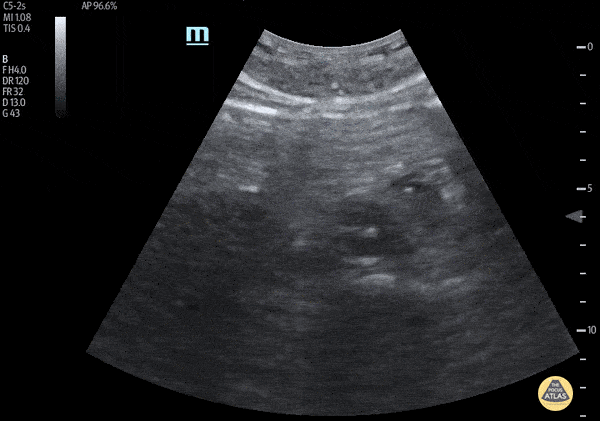

Aorta - Extensive Type B Aortic Dissection

A 60 year old man was transferred to a trauma facility after presumed mechanical ground-level fall. He was only able to answer yes/no questions, vital signs were normal and stable upon arrival. He denied abdominal or back pain. Upon arrival to receiving facility, POC ultrasound revealed intimal flap within the abdominal aorta extending from the subxiphoid region to the common iliac arteries. Bedside echo revealed no aortic root dilatation, pericardial effusion, or evidence of tamponade. CT scan confirmed thoracic and abdominal aortic dissection. Cardiothoracic surgery was notified immediately. POCUS can play a critical part in allowing for rapid diagnosis and can expedite patient-care, particularly in patients with altered mental status who cannot provide a more robust history. Quinn Fujii, DO Desert Regional Medical Center, Emergency Medicine